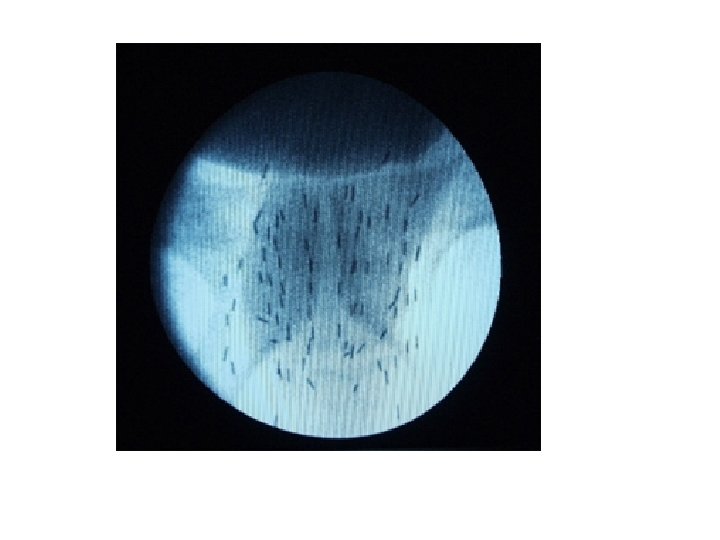

Брахитерапия